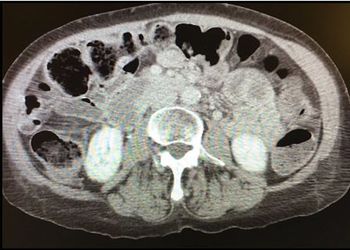

Severe epigastric pain radiating to the back in 2 patients and post-Whipple procedure complaints in another: 3 virtual puzzles in pancreatitis need solutions.

On hospital day 3, abdominal pain continues for the 57-year-old man, made worse by oral intake. Abdominal US suggests next steps. What would you do?

These symptoms are recurrent despite patient's adherence to enzyme replacement therapy for pancreatitis. Your next step?